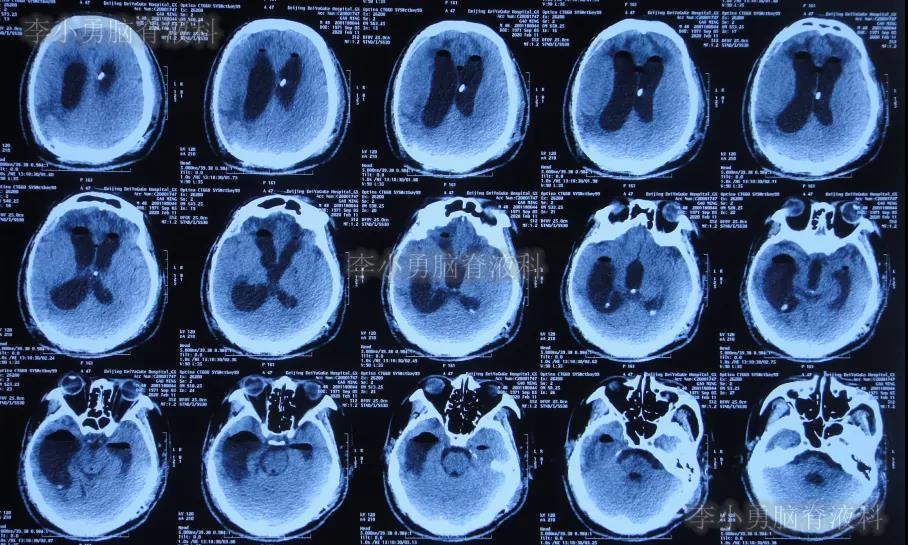

入院次日查头颅CT示颅骨修补术后,脑室引流后仍脑积水(图-9)。

图-9:2020年1月19日头颅CT

当天给予了拔除原脑室腹壁外引流管+脑室外引流术(图-10)。

图-10:2020年1月19日术后头颅CT

入院治疗24天即2020年2月11日,进行了脑室腹壁外引流术,术后当天查头颅CT(图-12)。

图-12:2020年2月11日头颅CT

入院治疗34天即2020年2月21日,查头颅CT示脑室进一步有缩小(图-13)。

图-13:2020年2月21日头颅CT

入院治疗69天即2020年3月27日,进行了脑室腹腔分流术(图-14)。

图-14:2020年3月27日脑室腹腔分流术后